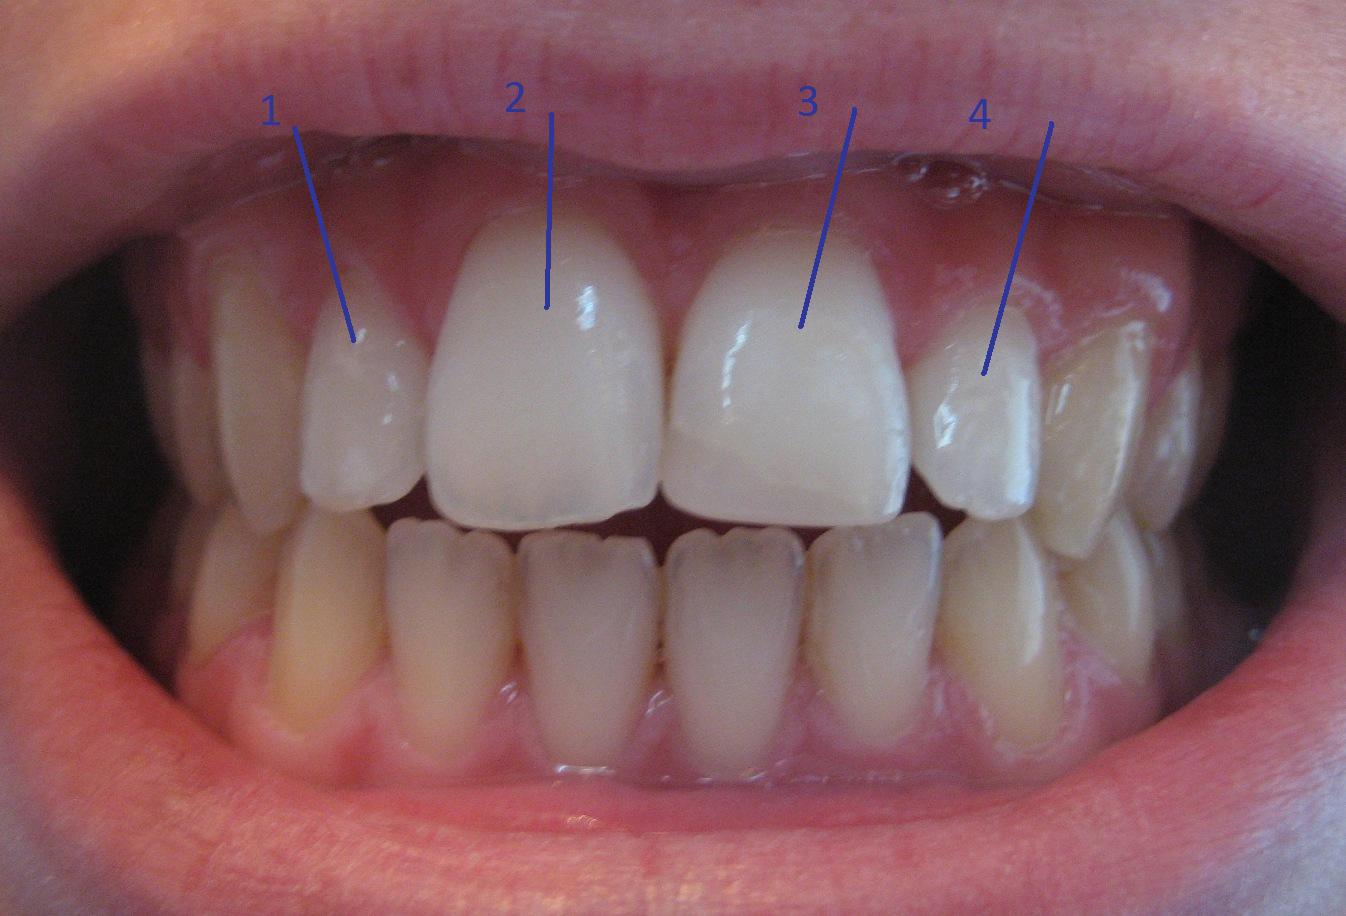

Ik heb me aangemeld op dit forum omdat ik graag wat informatie zou willen betreffende een cosmetische aanpassing aan mijn gebit, in het bijzonder mijn voortanden, en de tanden aan weerszijde daarvan. Dat zijn tanden 1, 2, 3 en 4 op de foto in de bijlage. Ik ben een 21 jarige man.

Als ik mijn tanden op elkaar zet, heb ik tussen mijn bovengebit en mijn ondergebit een soort spleetje. Ik heb een beugel gehad, maar het lijkt wel alsof mijn voortanden en de tanden daarnaast te kort zijn om net over mijn ondertanden te vallen (en zo hoort het toch eigenlijk? Is het niet?). Nu dacht ik altijd dat het verlengen van de tanden alleen mogelijk was door facings te plaatsen over je eigen tanden, en op die manier het spleetje te verhullen. Maar ik vind het doodzonde van mijn tanden om ze helemaal af te laten schaven om er vervolgens een facing over te plaatsen. Bovendien is het een zeer kostbare ingreep. Toen kwam ik de methode 'dental bonding' tegen. Hierbij kan met behulp van composiet de vorm van de tanden worden aangepast/verlengd. In mijn geval zou het gaan om enkele millimeters verlenging. Ik vond deze website met veel informatie over bonding, en over hoe mooi het gedaan kan worden.

Een goede cosmetische tandarts houdt helemaal rekening met de natuurlijke doorschijning van de tand en het natuurlijk kleurverloop (zoals te zien is op de voorbeelden op de website). Zoals te zien is op de site, kan het heel mooi gedaan worden. Ik heb ooit (inmiddels ongeveer 9 jaar geleden) een van mijn voortanden afgebroken (op de bijgesloten foto, tand nummer 3), die is ook gerepareerd met, naar wat ik aanneem, composiet door mijn tandarts. Ik heb mijn tandarts gevraagd over het verlengen van mijn tanden met composiet en hij zei dat het kon, echter hij is geen cosmetische tandarts, dus ik wil graag eerst even orienteren of ik niet beter naar een cosmetische tandarts kan stappen voor zo'n ingreep. Zoals te lezen is op de site mynewsmile.com, vergt het wat ervaring en kunde om een tand mooi te 'dental bonden' zodat 'ie ook weer een mooie natuurlijke doorschijning krijgt. Dit is niet meer het geval met het aangezette stukje tand op mijn voortand, zoals te zien op de foto.

Wat zijn geschikte tandartsen in het land die ervaren zijn in 'dental bonding' zoals te zien op de website in mijn post? Heeft iemand hier ervaring met de 'dental bonding' procedure met betrekking tot 'hervormen en/of verlenging van tanden'? Als jullie zo mijn tanden bekijken, denken jullie dan dat 'dental bonding' de meeste geschikte procedure is om dit (kleine) 'probleem' te verhelpen? En als laatste, je kan op de foto zien dat mijn ondertanden een kartelend randje hebben, is het aan te raden die af te slijpen? Zodat het mooi recht wordt?

Ik heb me aangemeld op dit forum omdat ik graag wat informatie zou willen betreffende een cosmetische aanpassing aan mijn gebit, in het bijzonder mijn voortanden, en de tanden aan weerszijde daarvan. Dat zijn tanden 1, 2, 3 en 4 op de foto in de bijlage. Ik ben een 21 jarige man.

Als ik mijn tanden op elkaar zet, heb ik tussen mijn bovengebit en mijn ondergebit een soort spleetje. Ik heb een beugel gehad, maar het lijkt wel alsof mijn voortanden en de tanden daarnaast te kort zijn om net over mijn ondertanden te vallen (en zo hoort het toch eigenlijk? Is het niet?). Nu dacht ik altijd dat het verlengen van de tanden alleen mogelijk was door facings te plaatsen over je eigen tanden, en op die manier het spleetje te verhullen. Maar ik vind het doodzonde van mijn tanden om ze helemaal af te laten schaven om er vervolgens een facing over te plaatsen. Bovendien is het een zeer kostbare ingreep. Toen kwam ik de methode 'dental bonding' tegen. Hierbij kan met behulp van composiet de vorm van de tanden worden aangepast/verlengd. In mijn geval zou het gaan om enkele millimeters verlenging. Ik vond deze website met veel informatie over bonding, en over hoe mooi het gedaan kan worden.

Een goede cosmetische tandarts houdt helemaal rekening met de natuurlijke doorschijning van de tand en het natuurlijk kleurverloop (zoals te zien is op de voorbeelden op de website). Zoals te zien is op de site, kan het heel mooi gedaan worden. Ik heb ooit (inmiddels ongeveer 9 jaar geleden) een van mijn voortanden afgebroken (op de bijgesloten foto, tand nummer 3), die is ook gerepareerd met, naar wat ik aanneem, composiet door mijn tandarts. Ik heb mijn tandarts gevraagd over het verlengen van mijn tanden met composiet en hij zei dat het kon, echter hij is geen cosmetische tandarts, dus ik wil graag eerst even orienteren of ik niet beter naar een cosmetische tandarts kan stappen voor zo'n ingreep. Zoals te lezen is op de site mynewsmile.com, vergt het wat ervaring en kunde om een tand mooi te 'dental bonden' zodat 'ie ook weer een mooie natuurlijke doorschijning krijgt. Dit is niet meer het geval met het aangezette stukje tand op mijn voortand, zoals te zien op de foto.

Wat zijn geschikte tandartsen in het land die ervaren zijn in 'dental bonding' zoals te zien op de website in mijn post? Heeft iemand hier ervaring met de 'dental bonding' procedure met betrekking tot 'hervormen en/of verlenging van tanden'? Als jullie zo mijn tanden bekijken, denken jullie dan dat 'dental bonding' de meeste geschikte procedure is om dit (kleine) 'probleem' te verhelpen? En als laatste, je kan op de foto zien dat mijn ondertanden een kartelend randje hebben, is het aan te raden die af te slijpen? Zodat het mooi recht wordt?